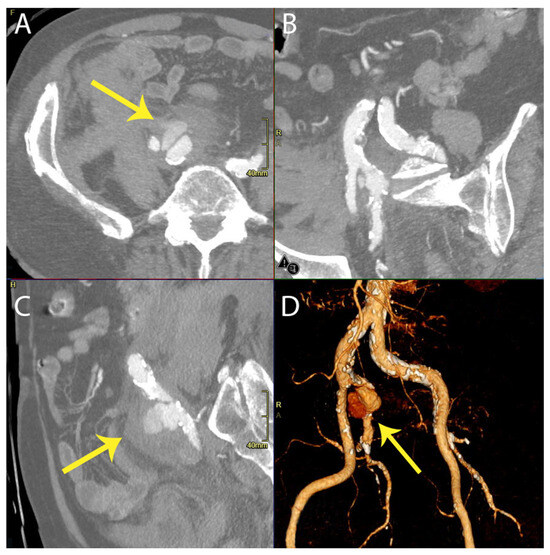

On the 30th postoperative day, the patient experienced a leakage from their rupture site that was a type Ia Endoleak (Figure 2), requiring an additional endovascular procedure to embolize the IIA and reline the common iliac and external iliac artery with an endograft.

Figure 2. Multiplanar reformation (MPR view in axial (A), coronal (B), sagittal (C)) and 3D reconstruction (D) of CT angiography demonstrating leakage from the right internal iliac artery rupture site due to a type Ia endoleak (highlighted with arrows).